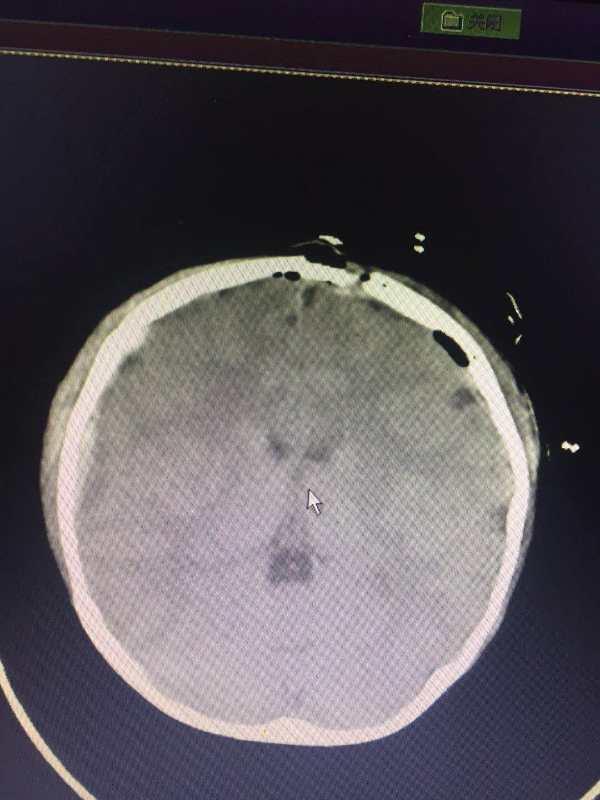

由于患儿从高处坠落造成颅骨凹陷性骨折,颅腔容积减小,左侧额叶受压明显,必须立即进行手术。但由于此类型骨折极易引起矢状窦大出血且患者年龄过小、出血耐受极差,如出血量稍多,很容易危及生命,因而手术困难程度不言而喻。

手术开始后,情况比想象的更为严重,数条骨折线、颅骨严重塌陷、冠状缝裂开并横跨矢状窦延伸到对侧。李淼医生仔细游离凹陷部分骨瓣,整复后还纳,整个手术过程十分顺利,出血量较少。在医护人员的共同努力下,手术顺利进行,患儿恢复较迅速,再无肢体抽搐症状。术后复查CT显示,颅内状况良好。看到患儿转危为安,吉大三院医联体的专家们脸上也露出了欣慰的笑容,医疗队安心踏上了回程的道路。